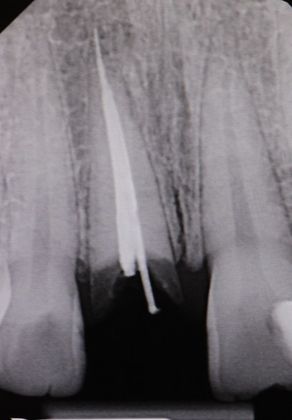

Dental Implants: Case 4

This beautiful girl presented to our Aiken office wanting to fix her front tooth. An immediate implant was placed and an immediate restoration was placed in its area. The smile was completed using an Emax implant crown much to the patient's satisfaction.